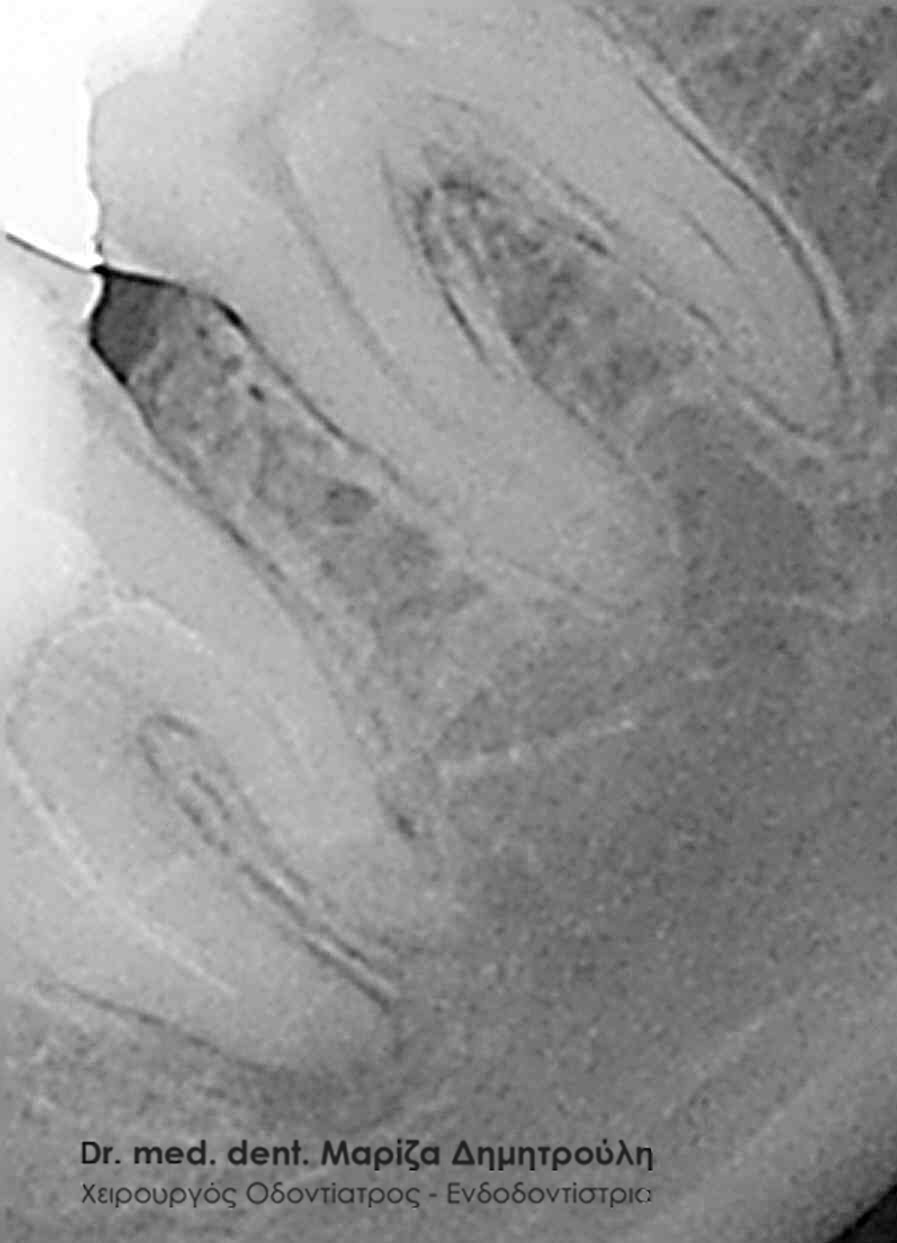

- με έντονα κεκαμμένους ριζικούς σωλήνες

με πολύπλοκη μορφολογία ριζών

Οι ενδοδοντολόγοι είναι οδοντίατροι με περαιτέρω πανεπιστημιακή ειδίκευση, η οποία διαρκεί τουλάχιστον τρία χρόνια μετά την απόκτηση του πτυχίου του οδοντίατρου. Ο ενδοδοντιστής έχει ειδικευθεί στην απονεύρωση δοντιών με ασυνήθιστη μορφολογία, με στενούς ή έντονα κεκαμένους ριζικούς σωλήνες, κ.α., περιστατικά δηλαδή που συνήθως δεν μπορεί να αντιμετωπίσει ένας κοινός οδοντίατρος. Ο ενδοδοντιστής, σε σχέση με έναν κοινό οδοντίατρο, χρησιμοποιεί κατά τη διάρκεια της απονεύρωσης ειδικές τεχνικές, εξειδικευμένα εργαλεία και υλικά, αλλά και προηγμένο τεχνολογικό εξοπλισμό. Δεν είναι λίγες οι περιπτώσεις που ένας ενδοδοντολόγος έχει καταφέρει να “σώσει” δόντια, τα οποία από έναν κοινό οδοντίατρο είχαν καταδικαστεί σε εξαγωγή. Απαιτητικά περιστατικά για έναν ενδοδοντιστή χαρακτηρίζονται δόντια με ενασβεστιωμένους (κλειστούς) ριζικούς σωλήνες όπως και δόντια που απαιτούν επανάληψη ενδοδοντικής θεραπείας / απονεύρωσης (δόντια δηλαδή που είχαν ήδη απονευρωθεί στο παρελθόν και παρουσιάζουν εκ νέου φλεγμονή και ίσως αλλοίωση στο οστό).